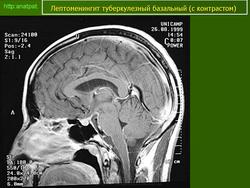

Туберкулёз.

Приложения:

1.t.slayd109.jpg2.t.slayd110.jpg3.t.slayd111.jpg